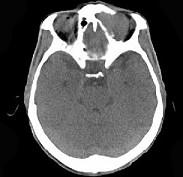

问题 男,53岁,左眼痛,突出3年,请结合影像,选择最可能的诊断 ( )

选项 A、眼型Graves病 B、良性混合瘤 C、骨膜下脓肿 D、黏液囊肿 E、淋巴瘤

答案 D